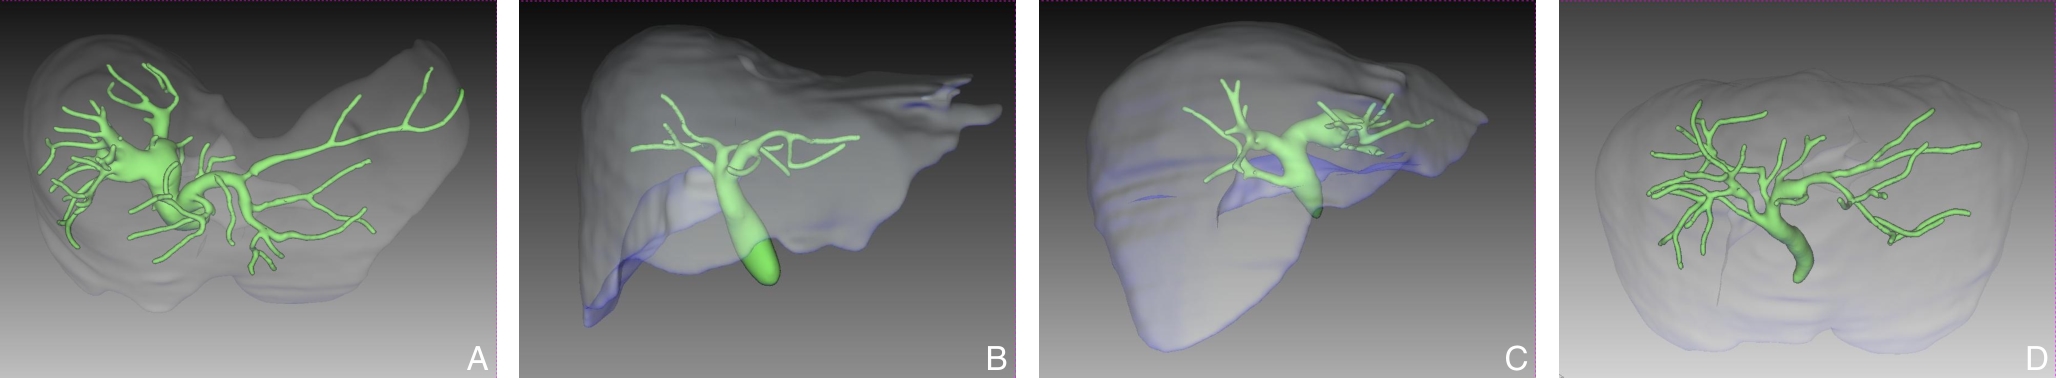

杨丽斐,武晓宁,钱叶蓉,刘鹏,任耀星,王傅民,张谞丰,吕毅,向俊西

2026,35(2):367-375, DOI: 10.7659/j.issn.1005-6947.260046

Abstract: